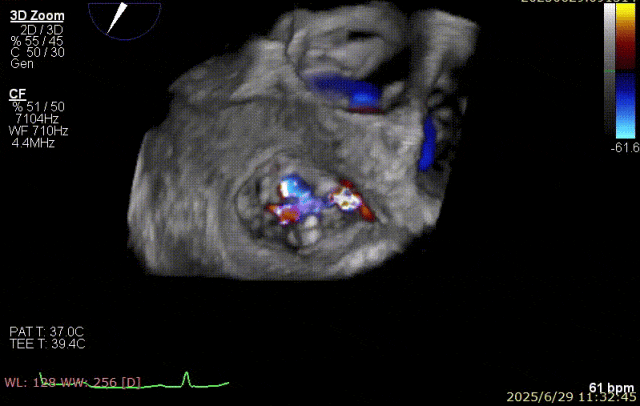

2025 年 6 月 29 日,经过对术前超声和 CT 影像进行深入分析,团队制定了周密手术计划。在麻醉手术中心副护士长刘菊梅的充分术前准备和中国医学科学院阜外医院欧阳文斌教授的指导下,凭借团队的紧密协作和娴熟操作,单纯利用超声影像精确引导,通过导引导管系统经右胸、右房,穿房间隔,建立到达左房通路;经该通路将两枚二尖瓣钳夹成功植入二尖瓣病变部位进行夹持,夹合器位于 3 区及部分 2 区,固定好,运动协调,瓣叶启闭灵活,瓣口轻度反流,二尖瓣平均跨瓣压差 2 mmHg。手术圆满完成。

器械植入后二尖瓣 AP 径约 35 mm,CC 径约 39 mm;夹合器固定好、组织桥稳定,前瓣夹闭后瓣叶长度 25 mm,后瓣夹闭后瓣叶长度 7 mm;二尖瓣开放好,瓣口呈大小双孔,二尖瓣瓣口面积约 2.8 cm²,平均压差 1 mmHg,关闭可,二尖瓣反流明显减轻(从术前反流 4+显著改善至 1+),手术全程无需体外循环支持,无需输血,无需射线全超声引导。患者术后第二日回普通病房,患者恢复良好,术后第五日即出院。

郑宝石教授介绍,经右胸小切口穿房间隔介入二尖瓣缘对缘钳夹治疗二尖瓣反流优势在于该入路减少过弯,对输送系统部件性能要求较低,手术路径短,钳夹调节简单准确且房间隔穿刺高度要求低于经股 TEER。另外,手术在全超声引导下完成,安全无射线危害;术前 3D 重建可在体外准确模拟手术路径。